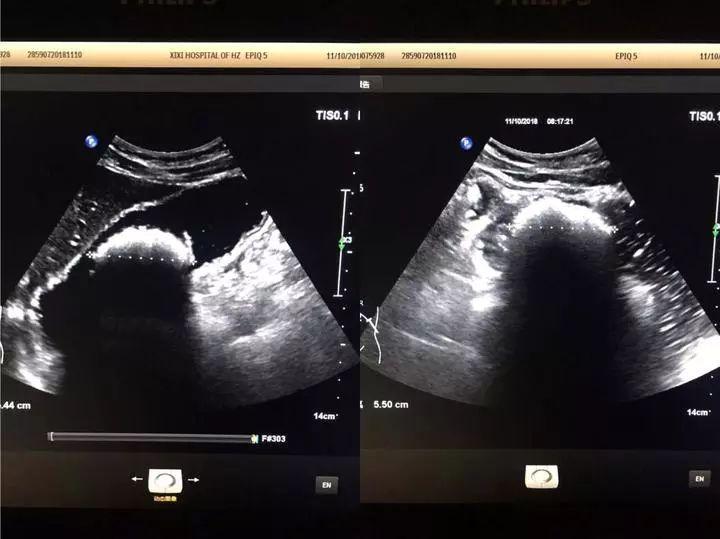

第三天,腹痛越加明显,小张如约赶到市西溪医院超声科,潘林医生给他仔细做了检查,肝脏、胆囊等脏器一个个查过来都没什么问题,一直查到腹部时,发现了一个“大家伙”,再放大镜头看,竟是胃里有个直径5.5cm的结石。

5.5cm是什么概念?成人握拳后拳头最长的径线一般为6—8cm,也就是说小张胃里有差不多拳头大小的石头撑在那里,所以总是肚子疼。

20181211043411290.jpg

亮亮的一团就是胃结石

就这样,什么罪都没遭,什么事也没耽误,每天只是比平时多喝了两瓶可乐,神奇的变化正在小张肚子里慢慢发生。三天后,他的腹痛症状缓解了;六天后,再复查B超,胃里的“大家伙”竟已不见踪影。